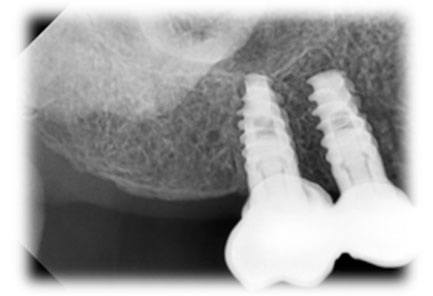

Guided Implant Surgery involves the use of advanced 3D imaging and computer-aided design (CAD) to plan the exact placement of dental implants. This meticulous planning process allows our dental specialists to visualize the patient’s oral anatomy in great detail, ensuring the implants are placed in the most ideal position for both functionality and aesthetics. The procedure is tailored to each patient's unique needs, ensuring a personalized treatment plan.

These technique assures that the implant is precisely placed without any damage to nerves, vessels and wouldn't perforate maxillary sinus too.